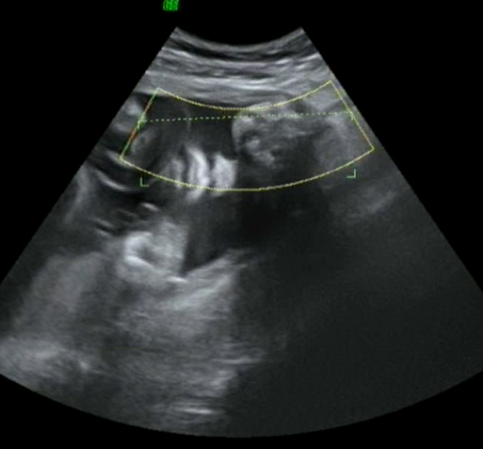

Ну как же))) так отчетливо видно губки и носик) вид буд-то снизу. Присмотритесь и включите воображение)))))))

Примерно по середине всё и носик, и губки...светлое пятнышко ближе к левому краю очерченного желтым поля. Ну как же...как же можно не видеть эти сладкие губки? ))))))))))))

Аааааа!!!!! А я во всем изображении пытаюсь лицо разглядеть))) думала увеличено просто все!!! А тут вон они где))) чудные губешки!!!

такие губы выразительные))) классно вам фоточка есть...делала в 34 недели, показали так же губки носик и щёёёёчки...но фотку не делают у нас в жк...((( так жаль

Это я сама сделала стоп-кадр с видео, мне видео записали маленькое) И то ребёнок никак не хотел личико показывать...как только датчик на лицо, сразу руки у лица))))))